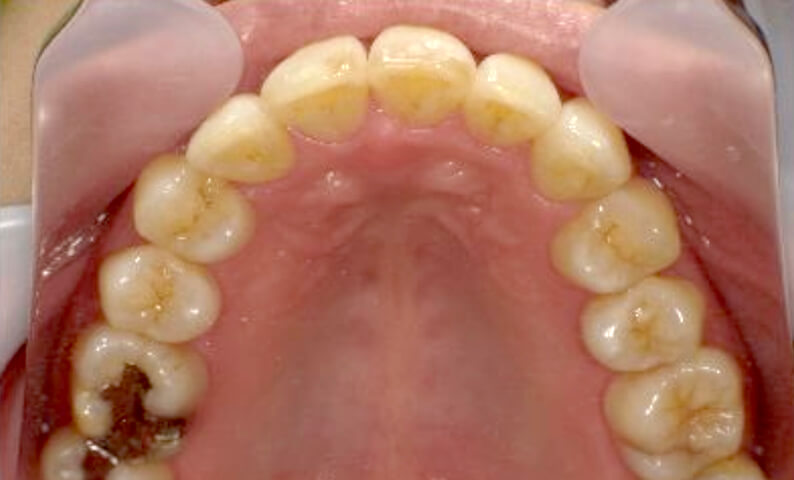

症例_001 下顎だけの部分矯正

治療期間:8ヶ月金額:21万円+税女性前歯のガタガタ下の前歯だけ

| Before | After |

|---|---|

|